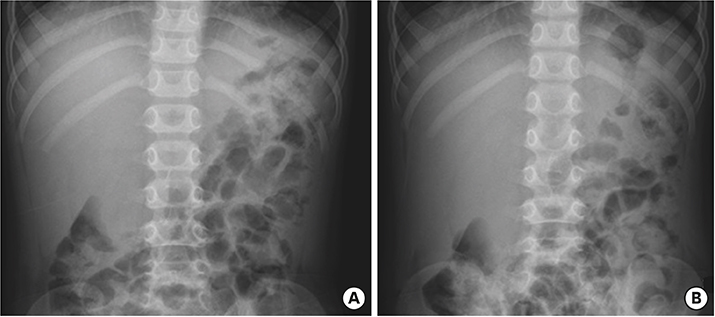

On the first day after admission, he received 2 g/kg IVIG and 50 mg/kg/day aspirin, following which his fever subsided and no further IVIG treatment was needed. His first echocardiography showed myocarditis (ejection fraction [EF], 45%) and mild ectasia of left main coronary artery (3.2–3.4 mm in diameter). On the second day after his admission, echocardiography (second follow-up) showed improved mild myocarditis (EF, 55%), improved ectasia of left main coronary artery (2.7–2.8 mm in diameter), and severe GB distension (8.9×4.6 cm in size), which possibly indicated GB hydrops (Fig. 2A). On the fourth day after his admission, although he had no fever and exhibited improvements in KD symptoms (i.e., eye injection, rash on abdomen, and cervical lymphadenopathy), he still complained of abdominal pain, distension, and tenderness of the RUQ. Follow-up laboratory findings were improved: neutrophilic leukocytosis (6,130 cells/mm3, with 33% neutrophils); decreased CRP (4.4 mg/dL), BNP (347 pg/mL), AST (40 U/L), and ALT (72 U/L); and improved hyperbilirubinemia (total bilirubin, 0.7 mg/dL). Echocardiography (third follow-up) showed normal completely improved carditis and still severe GB distension (10.2×5.5 cm in size) (Fig. 2B). Abdominal ultrasonography (US) was performed, which showed a markedly distended GB without stone, sludge, or wall thickening as well as normal bile ducts and liver morphology, which confirmed GB hydrops (Fig. 3A). On the sixth day after his admission, although his signs of KD had nearly disappeared, he still complained of abdominal discomfort, which had been moderately improving. The second follow-up abdominal US revealed a no notable change in GB distension compared to previous sonographic findings (Fig. 3B). An abdominal computed tomography (CT) scan was also obtained to exclude other hepatobiliary abnormalities, which showed similar findings as sonography, including a marked dilatation of the GB (8.0×5.5 cm in size) without stone, sludge, or wall thickening as well as normal bile ducts and liver morphology (Fig. 4). No complications necessitating surgical intervention had occurred and he was discharged 7 days after admission with only mild tenderness on the right upper-mid quadrant.

Fig. 2

Echocardiography showed severe gallbladder distension (A) 8.9×4.6 cm in size and (B) 10.2×5.5 cm in size.